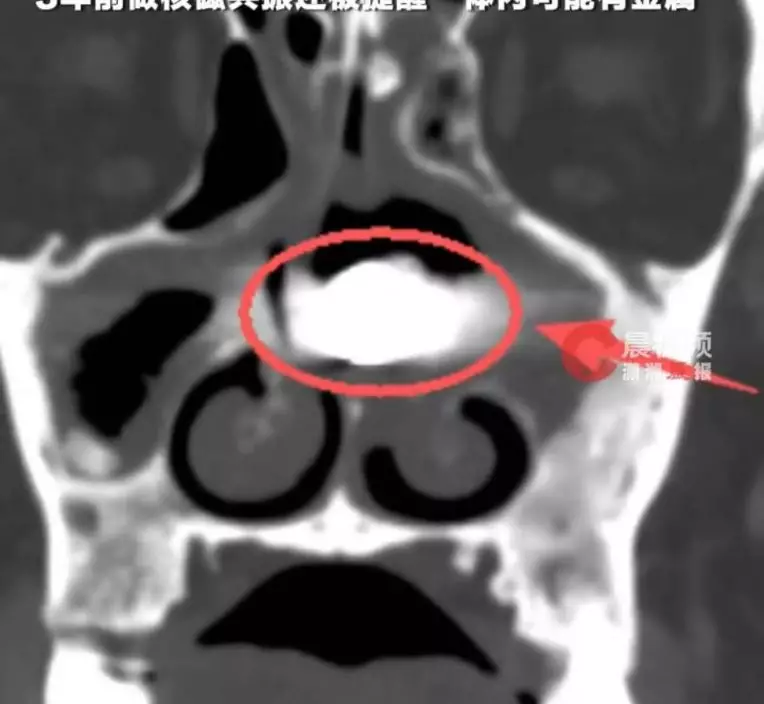

CT揭左鼻藏異物 手術取出生鏽螺絲釘

之後,林男接受電腦掃描(CT)檢查,結果發現左側鼻腔內藏有一個長約3CM的異物。3月10日,院方為他安排手術,最終順利將異物取出。由於該異物在鼻腔停留太久,早已被肉芽組織包裹,經確認後證實為一枚螺絲釘。